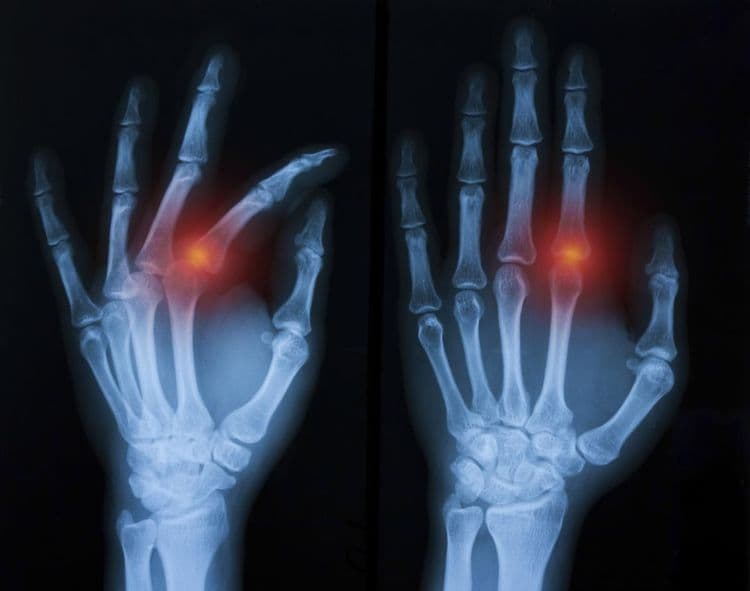

IntraArticular Fracture - हाडासोबतच सांध्याचा पृष्ठभाग सुद्धा फ्रॅक्चर होणे.

Pathological Fracture - आजारामुळे हाडे कमजोर होऊन तुटणे.